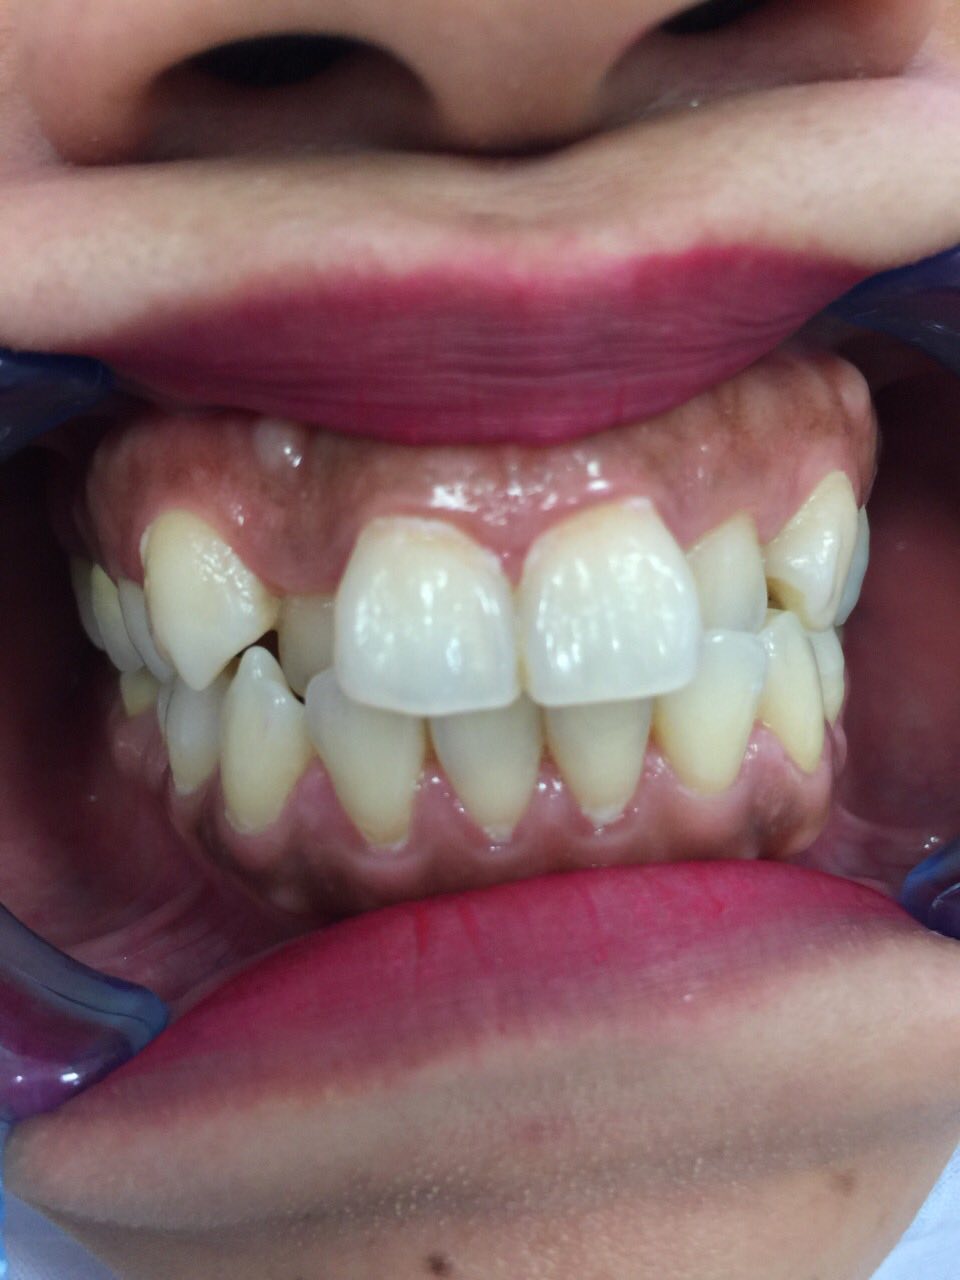

• Răng sứ thẩm mỹ

Bác sĩ Nguyễn Văn Hoàng Minh là người sáng lập ra Nha khoa Minh Nguyên. Là thành viên hiệp hội Implant thế giới ICOI (International Congress of Oral Implantologists thành lập từ năm 1972 tại Hoa Kì), Bác sĩ Nguyễn Văn Hoàng Minh đã tu nghiệp các nước Mỹ, Pháp, Đức,Thụy Sĩ, Hàn Quốc… và có hơn 25 năm kinh nghiệm chuyên cấy ghép Implant và chỉnh hình răng thẩm mỹ.